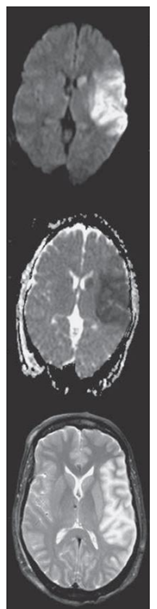

Observe a sequência de imagens Difusão, ADC e T2 em paciente

com Acidente Vascular Cerebral (AVC), adquiridas duas horas após

o evento.

A área afetada pelo AVC corresponde ao seguinte território vascular:

RM de paciente encontrado irresponsivo, com tempo de início dos sintomas desconhecido.

Baseado nesse exame, assinale a afirmativa correta.